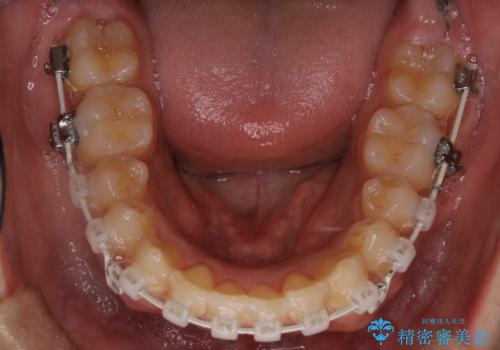

- 矯正装置

- 審美装置

- 歯並びの凸凹を主訴に来院されました。

スペースが必要なため、抜歯を行なって治療を行いました。

奥歯の捻れが強く治療期間がかかりましたが、綺麗な仕上がりに満足していただきました。

最初はインビザラインを治療していた経緯がありますが、使用時間が確保できずワイヤー矯正へ移行しております。